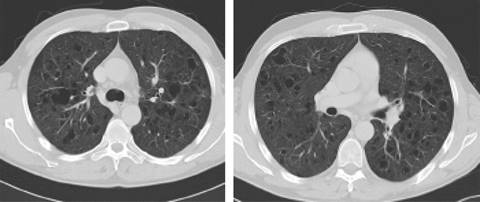

Se decidió realizar una tomografía computarizada (TC) para la valoración de otras posibles lesiones asociadas. El estudio puso de manifiesto de manera incidental la existencia de numerosas estructuras quísticas de paredes mal definidas con clara predominancia en ambos lóbulos superiores, asociando pequeños nódulos de distribución centrolobulillar. Los hallazgos radiológicos son sugestivos de enfermedad de histiocitosis de células de Langerhans pulmonar (Figuras 1 y 2).

Figura 1: Tomografía computarizada de alta resolución (TACAR), cortes axiales pulmonares. Se visualizan numerosas estructuras quísticas bilaterales de paredes mal definidas con clara predominancia en ambos lóbulos superiores, asociando pequeños nódulos de distribución centrolobulillar.